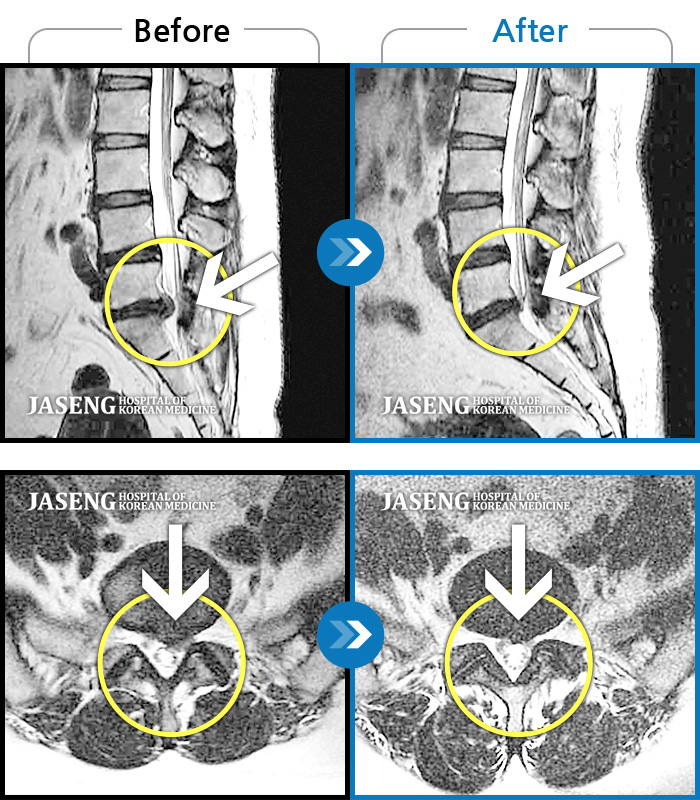

처음엔 이곳저곳 아파서 확실하게 어디가 아팠는지 몰랐는데 사고 후 일주일쯤 될 무렵 MRI촬영후 정확하게 진단을 받았습니다

허리디스크 2단계(초기) 진단을 받긴 했으나 다행히 근육량이 많아 모르고 살았는데 사고로 인해 디스크에 상처가 생겨 힘든 나날을 보내고 있습니다

디스크수술만 두번했어요 사고때문에 생긴 통증때문에 걱정이 많았어요 엄원장님 설명도 알기쉽게 해주시고 환자에대한 배려가 참 많은 분이셔서 많은 도움을 받고있습니다 적절한 치료처방으로 상태도 많이 호전되어 더 신뢰가가고 너무 감사해요 이렇게남아 감사의 글을 드립니다